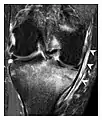

Occult osseous injuries may result from a direct blow to the bone by compressive forces of adjacent bones against one another or by traction forces during an avulsion injury. Lesions in the tibial plateau, hip, ankle, and wrist are often missed. In a tibial plateau fracture, any disruption of the posterior and anterior cortical rims of the plateau should be sought. Impaction of subchondral bone will appear as an increased sclerosis of the subchondral bone (Figure 1). In the hip, posterior acetabular fractures also present subtle radiographic findings. The acetabular lines should then be carefully examined keeping in mind that the posterior rim, which is harder to see on X-rays, is more frequently fractured than the anterior rim (Figure 2). In the wrist, detection of carpal bone fractures is often challenging, with up to 18% of scaphoid fractures radiographically occult. Carpal fractures, especially the scaphoid, are associated with the risk of avascular necrosis. In apparently normal wrist radiographs from symptomatic patients, if there is history of a fall on an outstretched hand with pain in the anatomic snuffbox, suggesting scaphoid injury, the initial examination with posteroanterior, lateral, and pronation oblique views must be complemented by other specific views such as supination oblique and the "scaphoid" view A careful examination of cortices for evidence of discontinuity or offset and cancellous bone for lucency is necessary (Figure 3).[1]

- a

- b

- c

Figure 1: A 56-year-old woman presenting with left knee pain after a fall. (a) Initial anteroposterior radiograph was considered normal, however, subtle cortical disruption of the anterior rim of the medial tibial plateau, medial to the tibial spine, is noted (arrow). (b) Coronal T1-weighted MRI confirms the cortical disruption (arrow) and shows extensive fracture through the proximal tibia. (c) Coronal proton density-weighted image with fat saturation shows extensive edema in the subchondral bone. Note also hypersignal adjacent to the medial collateral ligament corresponding to a grade I sprain (arrowheads).[1]